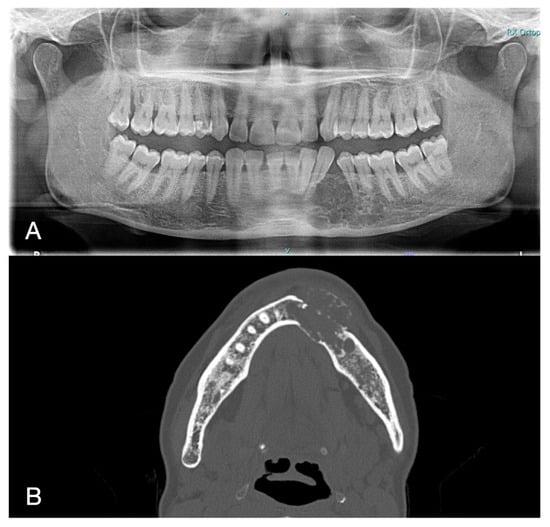

2. Case Report